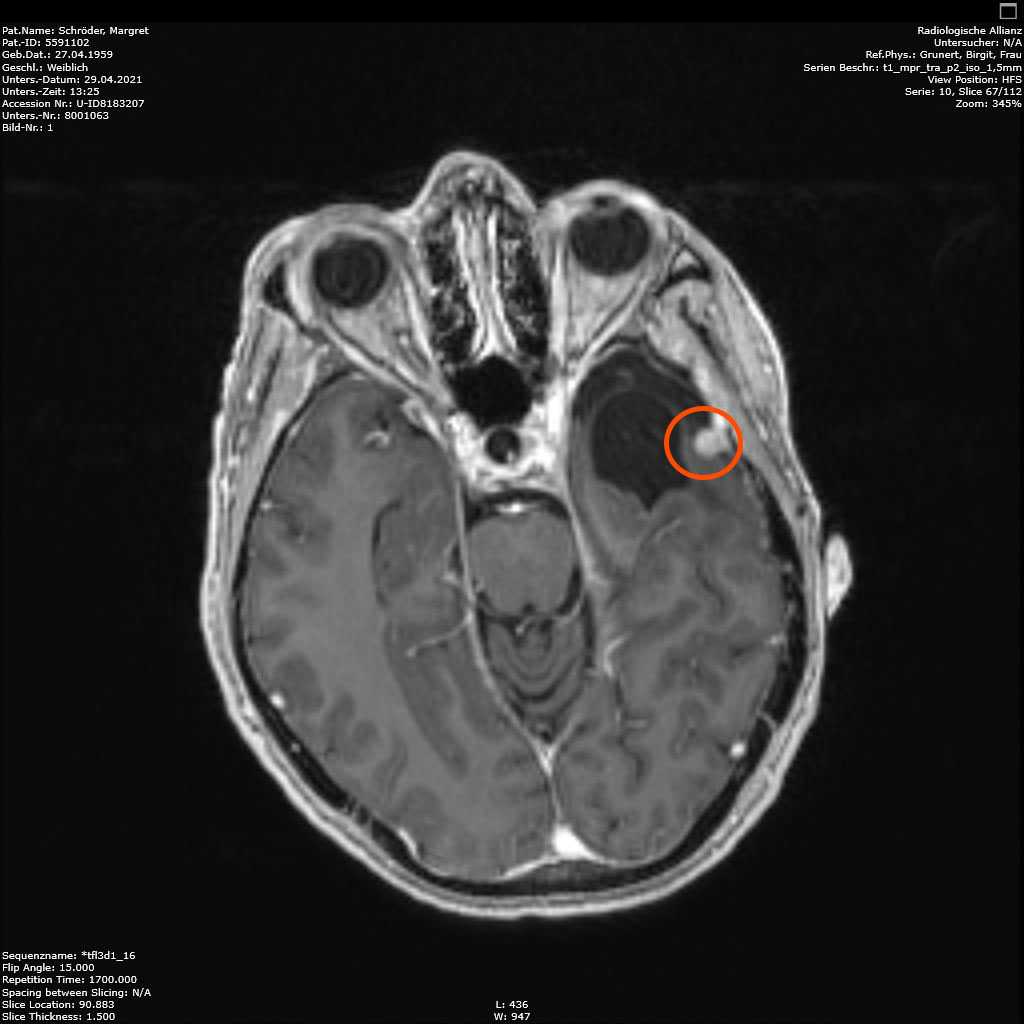

Am 29.4.2021 war ich zum Kontroll-MRT drei Monate nach der hochmodernen Strahlentherapie, dem Gamma-Knife. Leider ist das Ergebnis: den Tumor hat diese Behandlung nicht beeindruckt, keine Änderungen zu erkennen. Der Arzt schlägt eine weitere Kontrolle in 6 Monaten vor. Ich finde es etwas schwer, dieses Ergebnis einzuordnen. Aber so ist es nunmal. Vielleicht ist es ja normal, und wird erst später gut (siehe Punkt 4).

2. November 2021: Leider etwas gewachsen

Heute war ich im MRT im Bremen. Der Befund des auswertenden Arztes ist, dass er der Meinung ist, dass der Tumor etwas gewachsen ist. Ich habe mir die Bilder angesehen und versucht diese Aussage zu verstehen. Vermutlich ist sie richtig, aber das Wachstum ist nicht heftig nur vielleicht von 0,7 cm auf 0,8 cm. Aber Gamma-Knife hat es offensichtlich nicht entfernt.